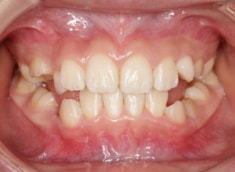

治療前

治療開始時